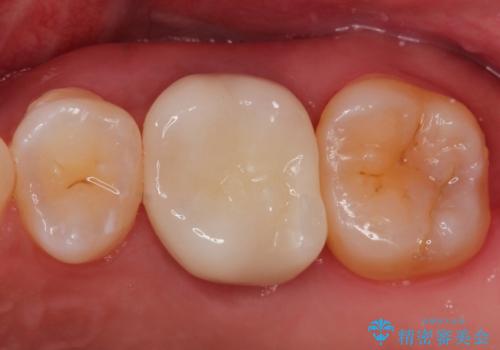

奥歯のむし歯を治したい セラミッククラウンによる補綴治療

奥歯の被せ物のやり直し 精密根管治療

大きい虫歯 根管治療〜オールセラミッククラウン